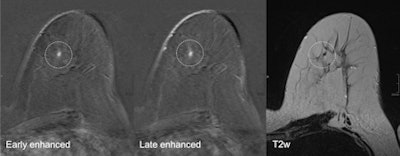

A 52-year-old patient who had breast cancer five years previously. MRI detected focus in the left craniomedial breast called BI-RADS 4, and a second opinion was requested. All images courtesy of Dr. Pascal Baltzer.

A 52-year-old patient who had breast cancer five years previously. MRI detected focus in the left craniomedial breast called BI-RADS 4, and a second opinion was requested. All images courtesy of Dr. Pascal Baltzer."Breast MRI is technically demanding, requiring excellent fat saturation, high spatial resolution, and rapid performance of postcontrast sequences," she said. "Common causes of false-positive diagnoses are represented by artifacts that can be related to the patient or to technical parameters."